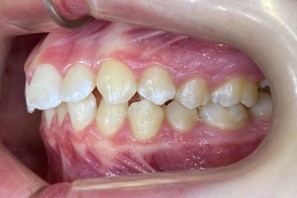

Chief complaint: We present the case of a 12-year-old female patient who came for an orthodontic evaluation, motivated by a family history of treatment. Clinical and radiographic analysis revealed a skeletal Class II malocclusion with molar and canine relationships also in Class II, moderate crowding in both arches, a deviation of the dental midline, and ectopic eruption of tooth 13. No functional issues with breathing or swallowing were observed, and oral health was generally good. A slight mandibular retrusion was noted in the soft tissue profile. A treatment plan was proposed using the Angel Aligner Pro system, aiming to correct dental misalignments and improve facial harmony through a minimally invasive, growth-adapted approach.

Clinical examination and diagnosis

- Woman ; 12/3 years

- Skeletal Class II

- Molar and canine Class II

- Upper and lower dentoalveolar compression

- Increased overjet and overbite

- Upper midline deviated 0,5 mm to the right

- Moderate upper and lower crowding